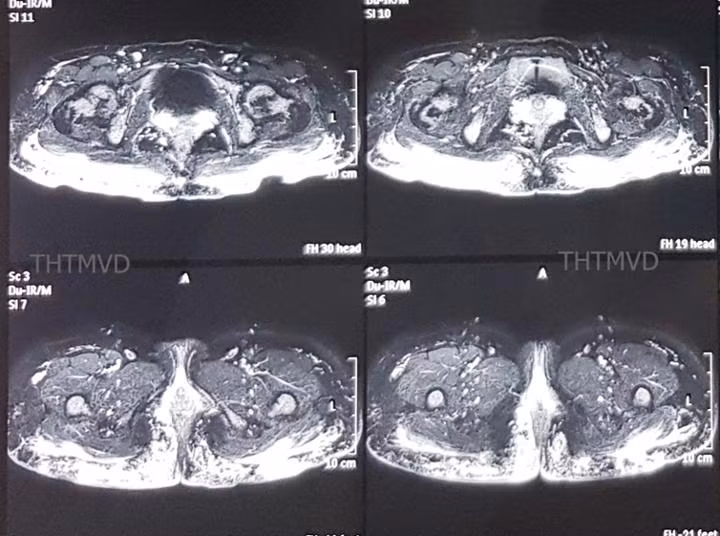

Phim cộng hưởng từ cho thấy viêm tấy lan tỏa. Ảnh bệnh viện cung cấp

PGS.TS Nguyễn Hồng Hà - Trưởng khoa Phẫu thuật – Tạo hình – Thẩm mỹ, Bệnh viện Hữu nghị Việt Đức cho biết, bệnh nhân vào viện trong tình trạng mệt mỏi, lo lắng, thiếu máu nhẹ. Vùng mông có hiện tượng viêm sưng nề nhiều, xen kẽ các vết thủng loét đã vỡ dò chảy mủ ra ngoài.  Phim chụp cộng hưởng từ MRI 3.0 cho thấy, hàng trăm khối u siliconoma cùng hiện tượng viêm lan tỏa trong lớp da cơ mông và thâm nhiễm đến gần hậu môn.